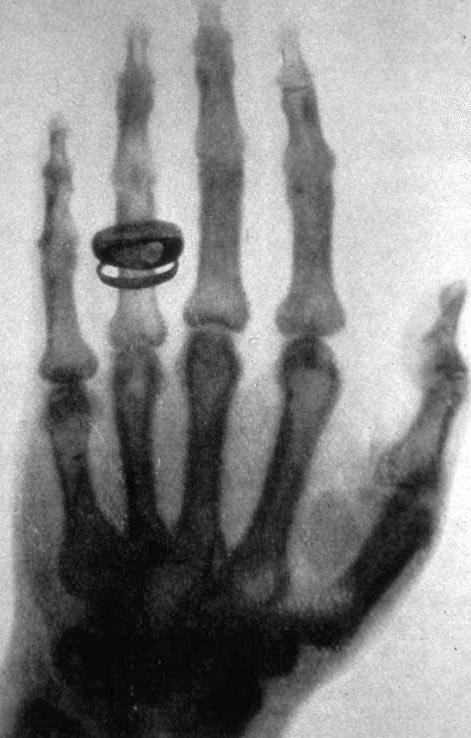

Anna sostenne sempre il marito con grande impegno e con tutte le forze che aveva. Quando Wilhelm trascorse sette settimane isolato nel proprio laboratorio verso la fine del 1895, non solo si prese cura di lui, ma si prestò anche ad essere la prima cavia di quella che sarebbe stata una delle più grandi innovazioni scientifiche. Fu la protagonista della prima radiografia della storia esponendo per 15 minuti la sua mano ai raggi X. Cosa apparve nell’immagine che venne registrata? Le ossa della sua mano sinistra con tanto di anello nuziale sull’anulare. Sconvolta per aver visto le proprie ossa mentre era ancora in vita, Anna non mise mai più piede nel laboratorio di suo marito.

prima-radiografia-rontgen.jpg